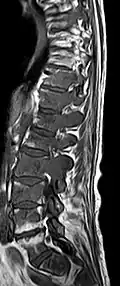

Imagerie par résonance magnétique

Avec l'IRM, on peut en particulier obtenir de bonnes images des tissus mous. C'est un processus idéal pour le diagnostic des métastases spinales (métastases des vertèbres). Avec l'IRM, on peut en outre rendre visible des complications supplémentaires dans la région des métastases spinales, comme des infections ou des blessures des tendons et ligaments, des œdèmes de la moelle osseuse après une fracture récente[120],[121], ou la compression de structures nerveuses[18]p. 16. Au moyen de séquences STIR, il est possible d'évaluer l'âge d'une fracture. Pour la détection des métastases, la pondération T1 avec des produits de contraste au gadolinium, comme l'acide gadotérique est particulièrement bien adaptée. Le produit de contraste s'accumule particulièrement fort dans les métastases[18],[122].

Pour le diagnostic des récidives (2), l'IRM est plus adapté que le scanner. Par exemple, les implants de titane font moins d'artefacts pour l’IRM[87],[123].

IRM natif avec pondération T1.

IRM sagittal natif avec pondération T1. On voit clairement l’extension jusqu'aux lames vertébrales.